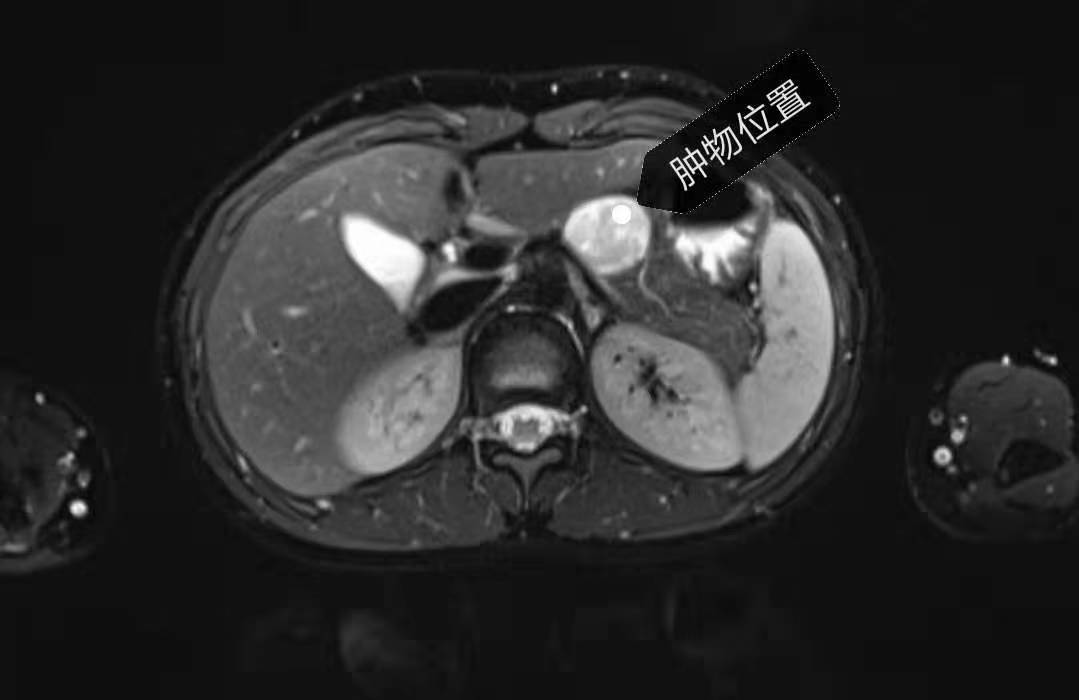

13岁女孩小叶(化名),由于上腹部胀痛难忍长达3个月,来医院检查后发现体内竟藏着一个3—4厘米大的胰体肿瘤,考虑“实性假乳头状瘤”可能,建议手术切除。常规的手术计划是连同胰尾和脾脏一并切除以降低难度,但创口面至少20公分以上。胰尾又含有大量的胰岛,切除后有患糖尿病风险。脾脏是人体的重要免疫器官,对维持人体正常血细胞水平、免疫功能等有重要作用。无论是从美观还是身体机能需要的角度,常规手术都不适合她。

由于脾动静脉与胰腺之间有许多的血管分支,一旦损伤极易造成脾脏坏死,小女孩的腹腔空间较成人相对更小,因此腹腔镜手术难度更大,对手术医生的技术要求也更高。经过充分的术前讨论,并制定周密的手术预案后,徐迪主任医师团队历时5小时,成功为患儿施行手术,仅留下4个1厘米大小的伤口。